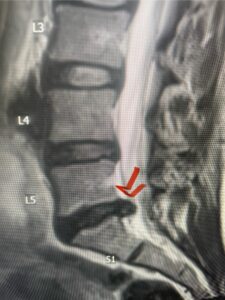

Another patient, a 77 year-old female, presents with pain, numbness, and weakness of her arms and difficulty with balance over a 6-month period. MRI revealed severe osteophytic disease at C5-C7 with cord compression (Fig. 4). Further work-up by fine-cut cervical CT to evaluate the nature of compression revealed a completely calcified osteophyte (Fig. 5). Although the patient had a good lordosis and a posterior cervical approach would accomplish an adequate decompression, we elected to perform a two-level anterior cervical discectomy and fusion. This particular osteophyte is formidable because of its size but the compression was all anterior and would be a less invasive approach. Fortunately, during the procedure, the patient had a fair amount of osteoporosis which allowed the osteophyte to be drilled and bit away with considerable ease. Interestingly, the C6 7 osteophyte which was more a sheet of osteophyte was more challenging to remove. In the end the decompression went well, and we placed two interbody devices filled with bone graft with plates at each level (Fig. 6). The patient had a nice recovery with immediate reduction of pain and numbness. This case demonstrates the importance of recognition of cervical myelopathy in its early stages. A significant reversal of function is generally the rule if the patient has appropriate correlative findings on exam and MRI, particularly with long tract distribution weakness development within a year time period.

Figs 4a: Sagittal and axial T2-weighted cervical MRIs demonstrating large osteophyte worse at C5-6 compressing spinal cord more eccentrically to the left (red arrows)

Fig 5a: Sagittal and axial cervical fine-cut CT scan demonstrating severe osteophyte formation causing cord compression at C 56 (red arrow)

Fig 5b: Sagittal and axial cervical fine-cut CT scan demonstrating severe osteophyte formation causing cord compression at C 56 (red arrow)